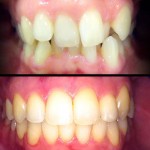

Casos Clínicos

Implantologia

Este é um caso mais simples de se fazer e com um valor (custo-benefício) bastante cómodo.São somente 4 implantes na arcada inferior suportando uma barra sobre a qual será transferido em parte o esforço mastigatório. É confeccionada em RESINA como uma prótese total convencional.